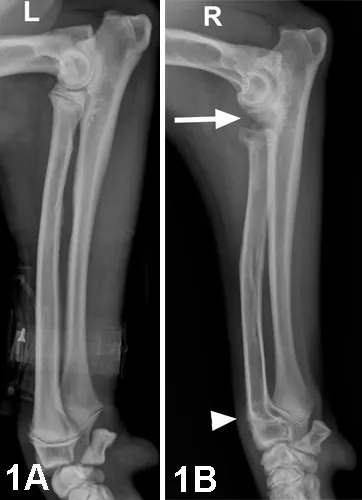

• Lateral views of the left (Figure 1A) and right (Figure 1B) radius/ulna show the left limb with normal, open physes in the distal radius and ulna, as well as the presence of an IV catheter.

• The distal right radial physis is closed (white arrowhead) and large gaps are present (white arrow) between the:

• (1) right humeral condyle and radial head, and

• (2) coronoid process of the ulna and radial head

Figure 1. Lateral views of the left (1A) and right (1B) radius/ulna.